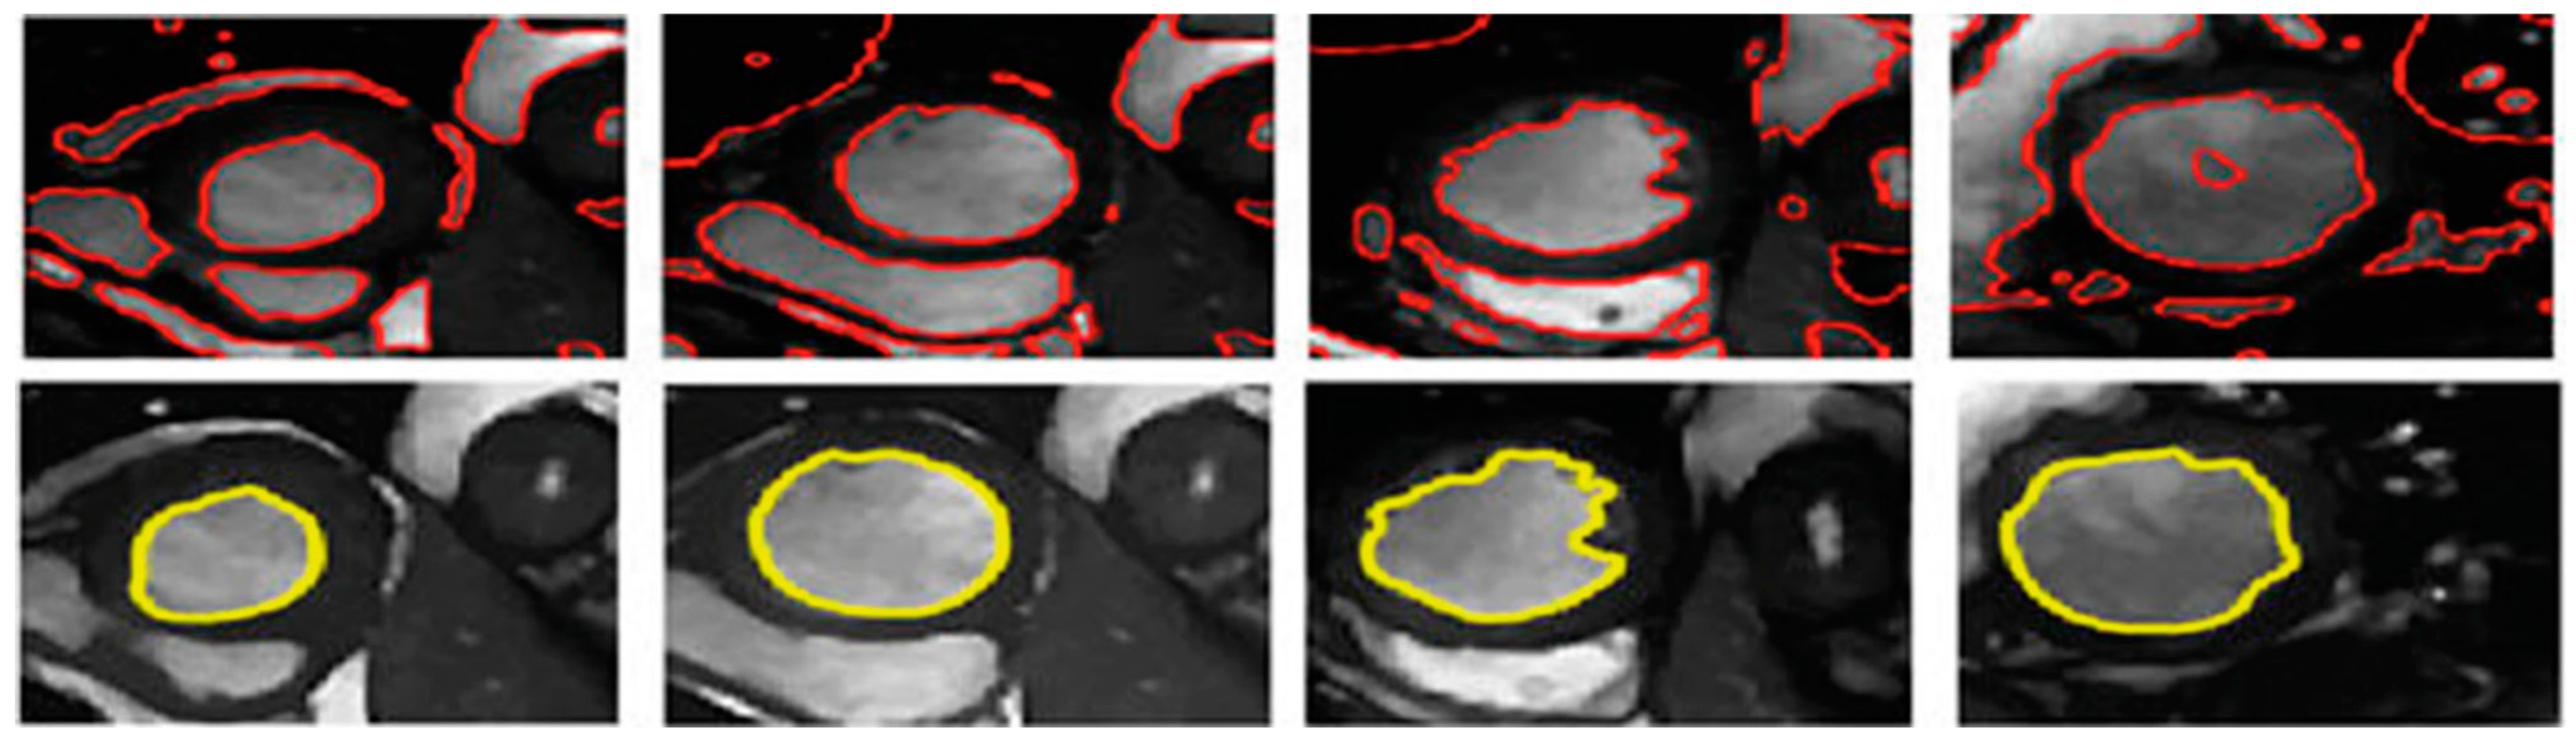

3.3. Illustrated Results

- U-Net with focal Tversky loss;

- U-Net with log-cosh dice loss;

- U-Net with Tversky loss;

- U-Net with dice loss; and

- U-Net with binary cross-entropy loss.